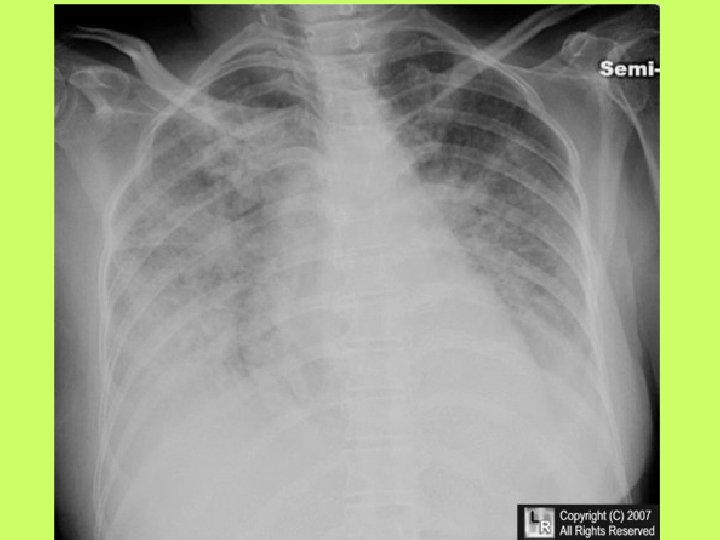

Noninvasive cardiac diagnostic studies 1 - EKG 2 -Chest X ray 3 -Exercise tolerance

Noninvasive cardiac diagnostic studies 1 - EKG 2 -Chest X ray 3 -Exercise tolerance test(ETT) 4 -Echocardiography transthoracic-trans esophagial 5 -Stress echocardiography 5 -Radionuclid imaging 6 -Cardiac catheterization